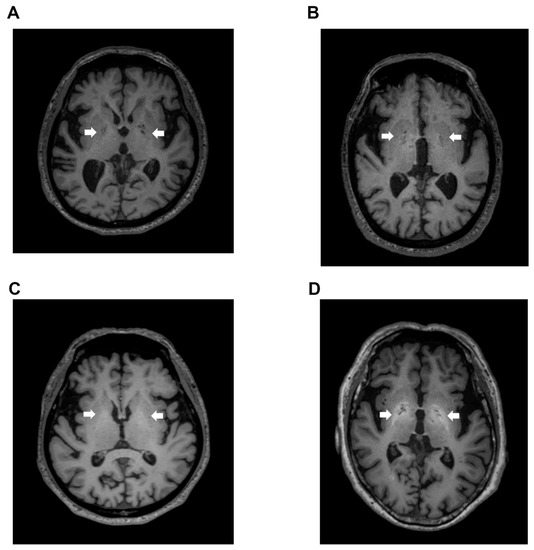

Using this index, we also examined the signal value distribution of the brain MRI images from 250 patients with Alzheimer’s disease, or vascular dementia, diagnosed at neurology clinics specializing in dementia. The mean age of the patients was 83.2  ±  6.1 years and 62.4% of the patients were female. Five dementia patients (2%) exceeded our established cut-off value. Therefore, we observed that our automatic assessment of signal intensity in GP is useful to distinguish LC patients with HE from healthy subjects and those without HE. Conversely, signal intensities of GP within the dementia group were markedly decreased; this finding may reflect ischemic changes in the basal ganglia, particularly in patients with vascular dementia (Figure 3). Through a follow-up medical history assessment, it was discovered that one out of five patients who exceeded the cut-off index had undergone liver resection due to hepatocellular carcinoma, and patient biochemical data revealed mild thrombocytopenia (11.3 × 104/MCL), mild elevation of transaminases (AST 45 IU/L and ALT 36 IU/L) and diabetes (hemoglobin A1c 7.1%). This patient displayed severe cerebral atrophy and bilateral symmetric hyperintensities of the GP in T1-weighted images (Figure 4A). The GP intensity histogram of this patient was similar to that of an LC patient with HE (Figure 4B), suggesting the possibility of an unknown hepatic factor concomitant with Alzheimer’s disease. We were unable to confirm obvious signs of LC nor acquire detailed residual data for these four patients.

Figure 4. Globus pallidus (arrow) in T1-weighted image. (A) Transverse T1-weighted imaging and (B) signal intensity histograms of a 76-year-old female patient with Alzheimer’s disease and a history of liver resection due to hepatocellular carcinoma and an HE patient (68-year-old male). Biochemical data from this dementia patient revealed mild thrombocytopenia (11.3 × 104/MCL), mild elevation of transaminases (AST 45 IU/L and ALT 36 IU/L) and diabetes (hemoglobin A1c 7.1%). HE, hepatic encephalopathy; AST, aspartate aminotransferase; ALT, alanine aminotransferase.